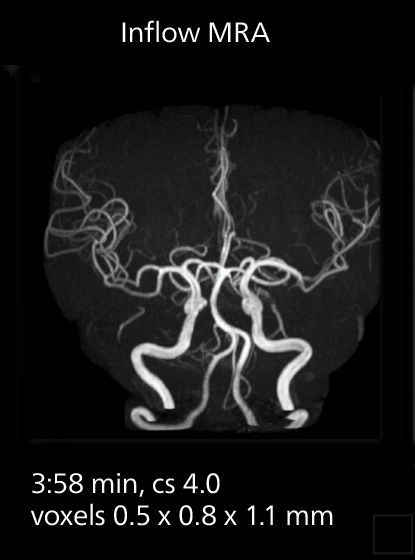

These images of an old cerebral infarction demonstrate the speed and image quality after upgrading to Elition X.